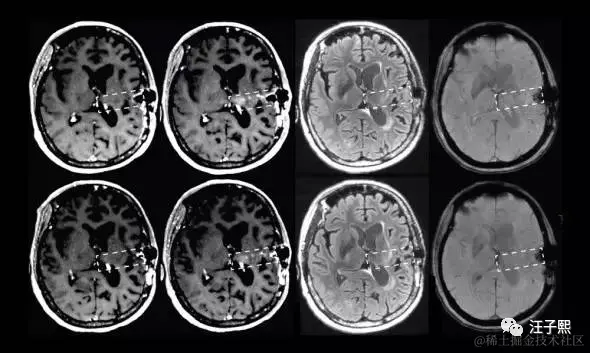

Jerry之前的文章 记一次SAP开发工程师给微软Azure报incident的体验,也提到自己处理incident和给别的程序员报incident的经历,没想到,这次有医生给我身上这台生物系统报了incident,而且priority还是very high的。一个专业的程序员,在接到incident之后,都是从“问题重现-问题定位-设计解决方案-处理问题-测试”这几个步骤进行的。我最近,凭着Google和金山词霸,也在看相关的英文论文,从病的诱因,诊断,治疗和预后这几个方面来学习,恶补了一大堆理论知识,虽然对我实际可能没什么用,甚至会让我的情绪变得消极,然而我的这些行为都是一个程序员的职业习惯使然——不管遇到什么问题都想刨根究底。

如果说计算机学科的论文少不了各种公式,那么医学界的论文则充斥着各种数字,百分比,曲线图,这些冷冰冰的统计学上的数字看了让人不寒而栗。